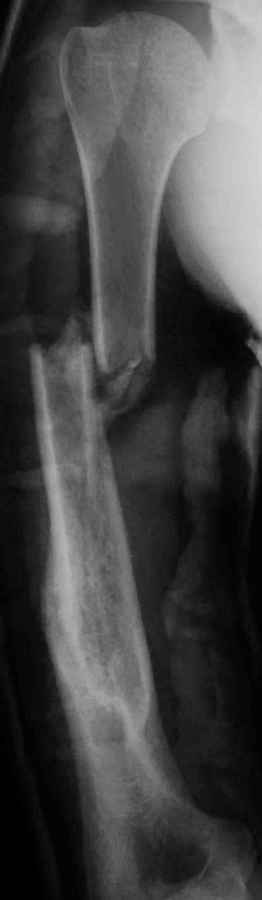

Результат консервативного лечения короткого косого перелома диафиза плеча врачами общей практики в условиях развивающейся страны у больного low social class

Предыдущий перелом плеча – пару лет назад ДТП. К сожалению, этот крайне важный жизненный опыт не изменил стиль вождения больного Последний перелом плеча – ДТП 2 мес назад. В связи с дефицитом как специалистов – ортопедов, так и операционного времени в принципе больной был осмотрен в приемном покое врачом общей практики, наложена U-образная гипсовая повязка и отправлен домой. Я впервые увидел больного через 6 нед после травмы, сделал снимки и снял повязку. Фотографии больного - 2 мес после травмы. снимки - при травме и через 6 недель

Вывод: Если плечо не трогать, оно нормально срастается.

Тот же самый вывод наукообразно: данное клиническое наблюдение свидетельствует, что консервативное лечение переломов диафиза плеча является патофизиологически оптимальным, приводит к удовлетворительному функциональному результату и явлеяется наиболее экономически щадящим как для больного, так и для системы государственного здравоохранения в целом.